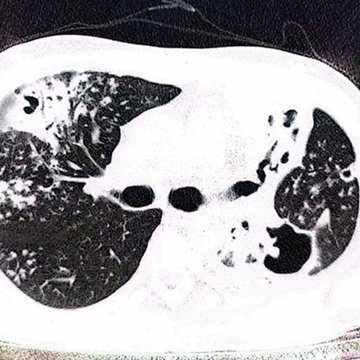

Jediný nález pochází od pacienta z Íránu, u kterého v roce 2022 způsobil invazivní plicní aspergilózu. Konkrétní pacient byl léčen pro tuberkulózu a jeho organismus byl také zatížen závislostí na opiu.

Mezi nejčastější patří zánět zvukovodu, zánět oční rohovky nebo invazivní aspergilóza. U zdravého člověka se poslední jmenované závažné onemocnění, nejčastěji postihující plíce, nerozvine, neboť imunitní buňky vdechnuté spory odstraní. U člověka s oslabenou imunitou ale mohou spory klíčit a růst v plicní tkáni, která se stane pro houbu zdrojem živin.

„Nejvíce příbuzný druh, A. brasiliensis, který byl také několikrát zachycen jako patogen, vykazuje i odlišné citlivosti k antimykotikům. Aspergillus hubkae je totiž rezistentní k léčivu itrakonazol, kdežto A. brasiliensis je citlivý. Protože je ale nový druh zatím známý jen z jednoho klinického případu, je nutné všechny atributy v budoucnu ověřit u většího počtu izolátů. Není totiž jasné, jak velká může být vnitrodruhová variabilita ve jmenovaných znacích,“ dodává Vít Hubka.